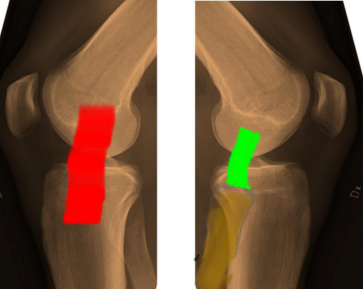

The two ligaments in the knee: the medial collateral ligament (MCL) and the lateral collateral ligament (LCL). Medial ligament injuries are most often caused by impact to the outside of the knee, called valgus forces. Ligament injuries can occur alone but are often associated with anterior cruciate ligament (ACL) and/or posterior cruciate ligament (PCL) injuries. Gender: Described as two matchsticks held together by rubber bands. These "rubber bands" are four major ligaments: two cruciate ligaments, the anterior cruciate ligament and posterior cruciate ligament, and two accessory ligaments, the medial and lateral ligaments (Figures 1 and 2).

Figure 1: Schematic AP drawing of the medial (red) and lateral (green) collateral ligaments.

Figure 2: Schematic lateral drawing of the medial (red) and lateral (green) collateral ligaments.